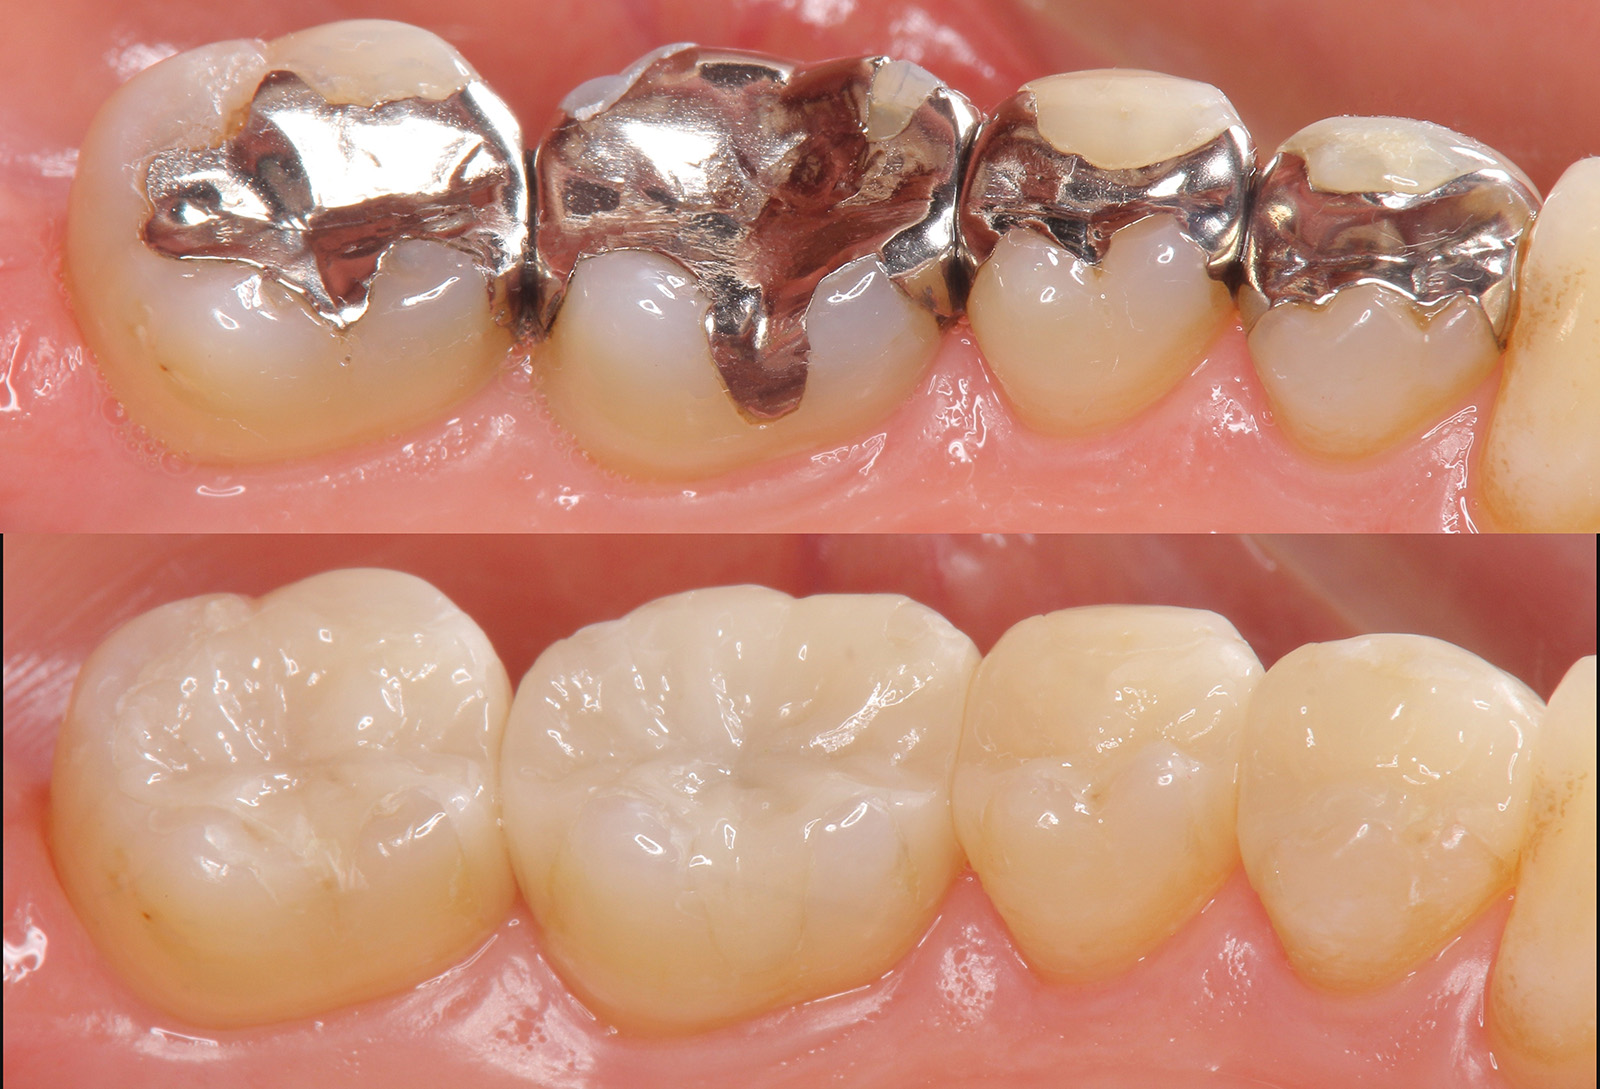

銀歯の詰め物・被せ物を、e-maxのインレーやクラウンに置き換えた症例。

ガラス系のセラミック素材です。歯に近い透明感があり、自分の歯と同じような美しさが特徴です。汚れを弾くため、虫歯や歯周病になりにくく、変色もしにくいというメリットもあります。